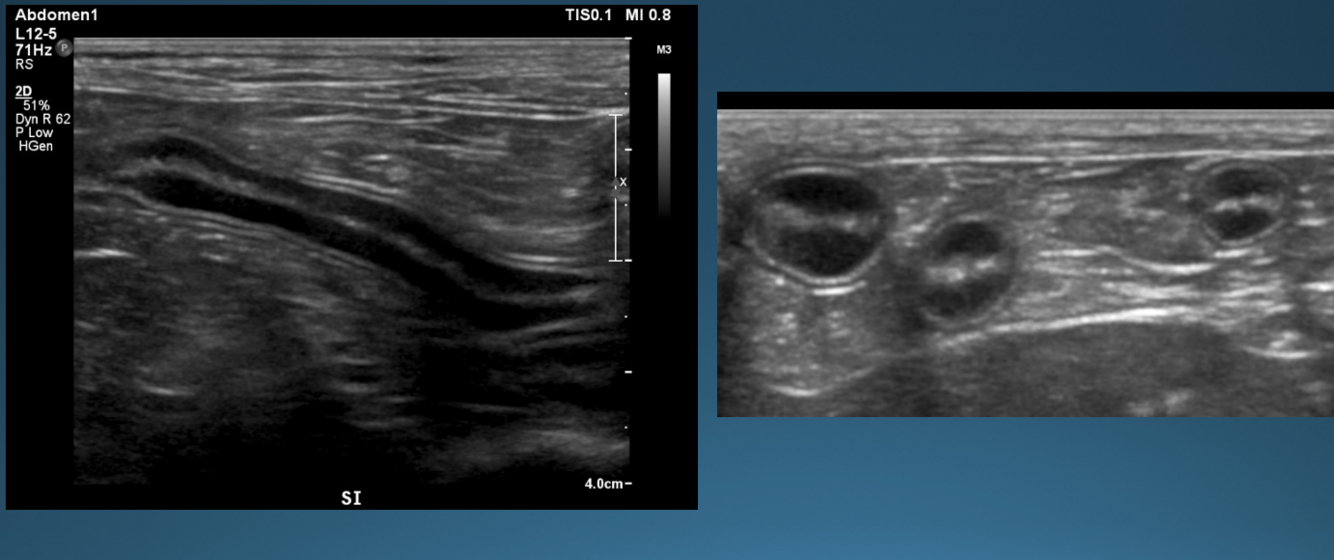

What is shown in these images?

A

normal stomach

-presence of rugal folds

-ability to assess gastric wall